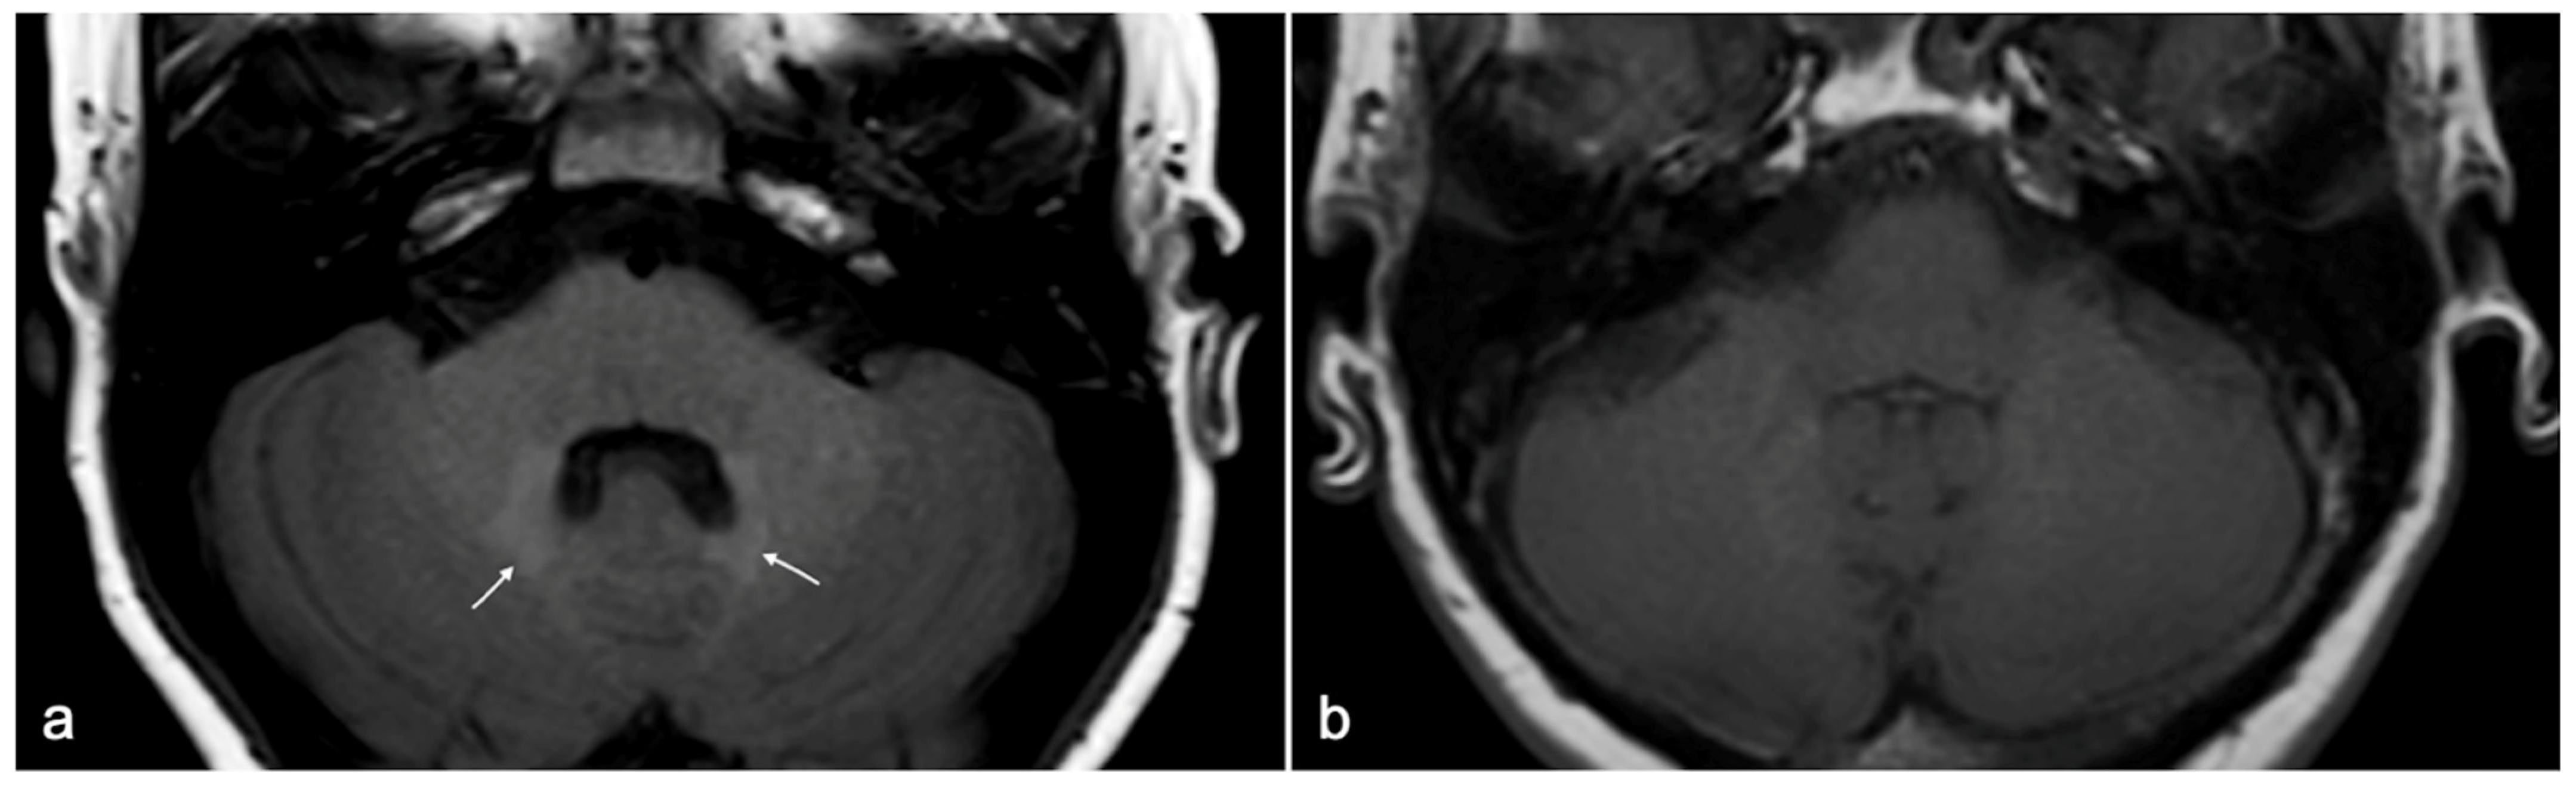

Gadolinium retention in bones, liver, and skin has been assessed with histology, as well as the one observed in the kidney (specifically in patients with NSF), but it cannot be detected using MRI. Gadolinium retention in brain tissue, although confirmed in several post-mortem studies, can also be observed at MRI examinations as a focal T1-weighted hyperintensity in specific central nervous system (CNS) regions [51,54,55]. Among the above-mentioned deposition sites, the most striking and groundbreaking reports first concerned gadolinium retention in CNS [56,57], the only one that can be observed in vivo by means of MRI examination as spontaneous unenhanced T1-weighted hyperintensity in the dentate nuclei and globus pallidus (Figure 9). The phenomenon is not limited to patients with blood–brain–barrier disruption; it is apparently dose-dependent and is more likely to occur with linear rather than with cyclic GBCAs [51].

Figure 9. (a) Example of spontaneous T1w hyperintensity due to gadolinium deposition within dentate nuclei (white arrows) at 1.5 T MRI in a 25-year-old patient diagnosed with tuberous sclerosis who has undergone multiple Gadobutrol administrations over years. (b) Age- and sex-matched normal control for comparison.